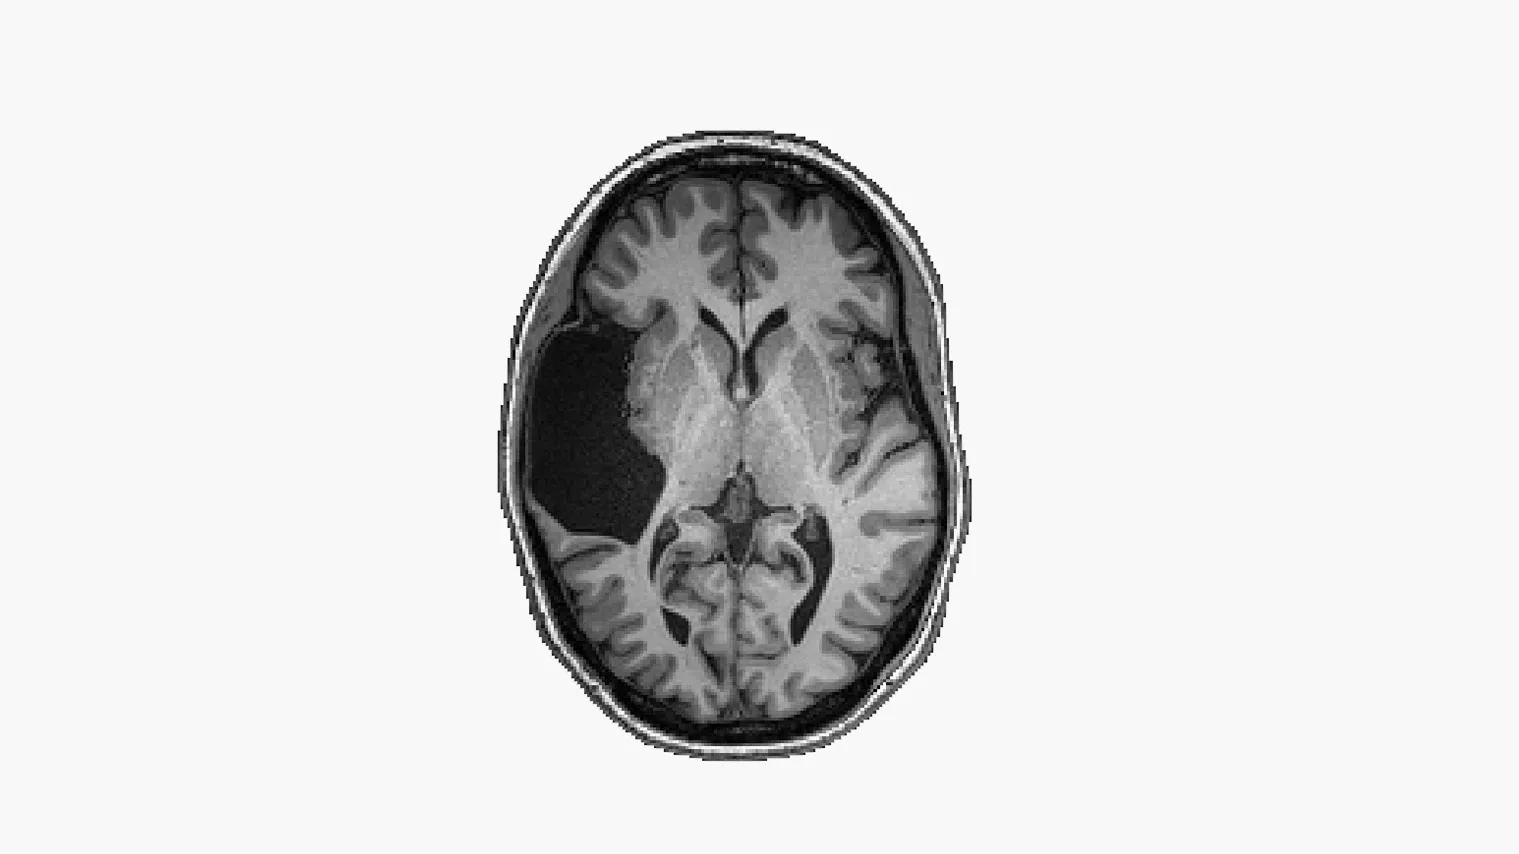

In the world of neuroscience and human cognition, every individual’s brain is a unique puzzle waiting to be solved. Elyse G. embarked on a remarkable odyssey, an extraordinary journey into the depths of her own mind, with one intriguing missing piece. In this article, we invite you to join the community of News and Updates Seekers as we delve into Elyse G.’s Brain Odyssey, guided by the insights of Dr. Fedorenko’s team. Together, we will uncover the secrets of the human brain, the power of resilience, and the pursuit of knowledge.

Elyse G., a woman with an insatiable curiosity and an indomitable spirit, found herself facing an enigma that captivated her thoughts. A specific aspect of her brain’s function eluded her understanding, a puzzle piece missing from her cognitive puzzle. But rather than succumbing to frustration, Elyse embarked on a courageous journey of self-discovery.

Elyse’s journey serves as a microcosm of the broader quest to understand the human brain’s intricate dance of cognition and language. Dr. Fedorenko’s team’s expertise illuminates the neural pathways, linguistic processing, and cognitive intricacies involved in Elyse’s unique case.